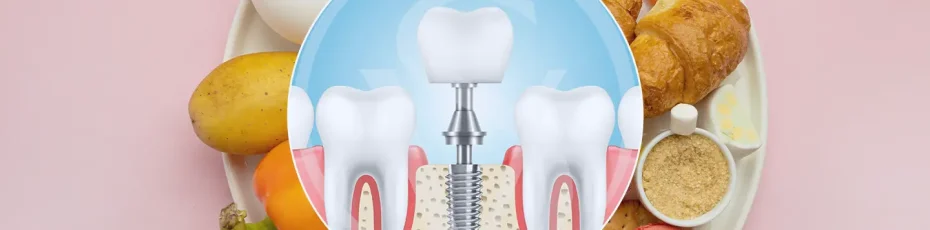

Getting dental implants is a major step toward restoring your smile, confidence, and overall oral function. While the surgical procedure itself is critical, what happens afterward, especially in terms of diet, is just as important for a smooth and successful recovery. If you are weighing the advantages versus the disadvantages of dental implants in Colwood, […]